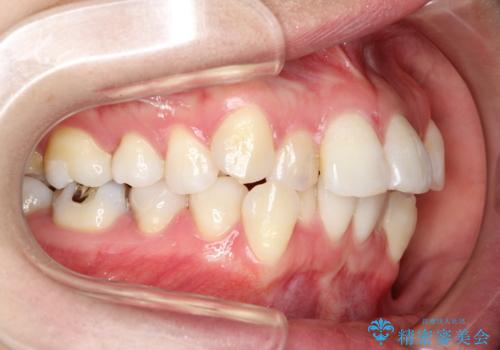

- 前歯のデコボコと上顎の前突感による口の閉じにくさを気にして来院された患者様です。

目立たない装置を希望されたので、上顎が裏側装置のハーフリンガルを選択し、上下左右の小臼歯(計4歯)を抜歯して矯正治療を行うこととしました。

期間はかかったものの、口元の張り出し感や歯のデコボコが解消され、患者様には大変満足していただけました。